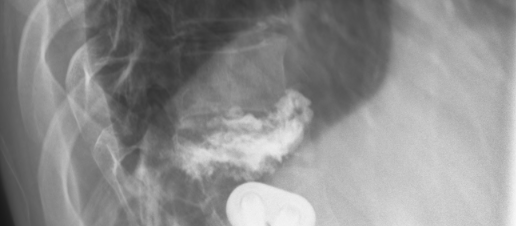

It’s been about a month since the doctors were able to perform a pretty miraculous procedure on my back. The accident burst my T11 vertebrae and since I already have a fusion and plates from T12-L2 the initial diagnosis was that to keep the spine supported they were going to have to fuse from T9 or T10 all the way down to L3 or L4 with the addition of rods/plates going from top to bottom of those locations. I told Dr. Sipos that I would prefer not to have such an invasive surgery and if he had any other options, initially he said that there was to much damage and that this was going to be the most feasible option, so I asked him to take a day or so and see if he could come up with any other options. He came to me the next day and said he had one other option of (for lack of better terminology) cementing the T11 vertebrae, removing all the extra bone fragments, and grinding down the portions that were pressuring the spine. It was not certain that it would work because of the amount of current injury and past injury, so he asked if I would like to take that option but if when he was performing the surgery he was not able to complete that option he had my permission to go with the full fusion from top to bottom as explained above. Of course I agreed and hoped for the best.

Needless to say his amazing talent worked out and he was able to perform the rebuilding of that vertebrae without having to insert and extra metal or fusions. Here are some pictures of what he was able to do and my current back.